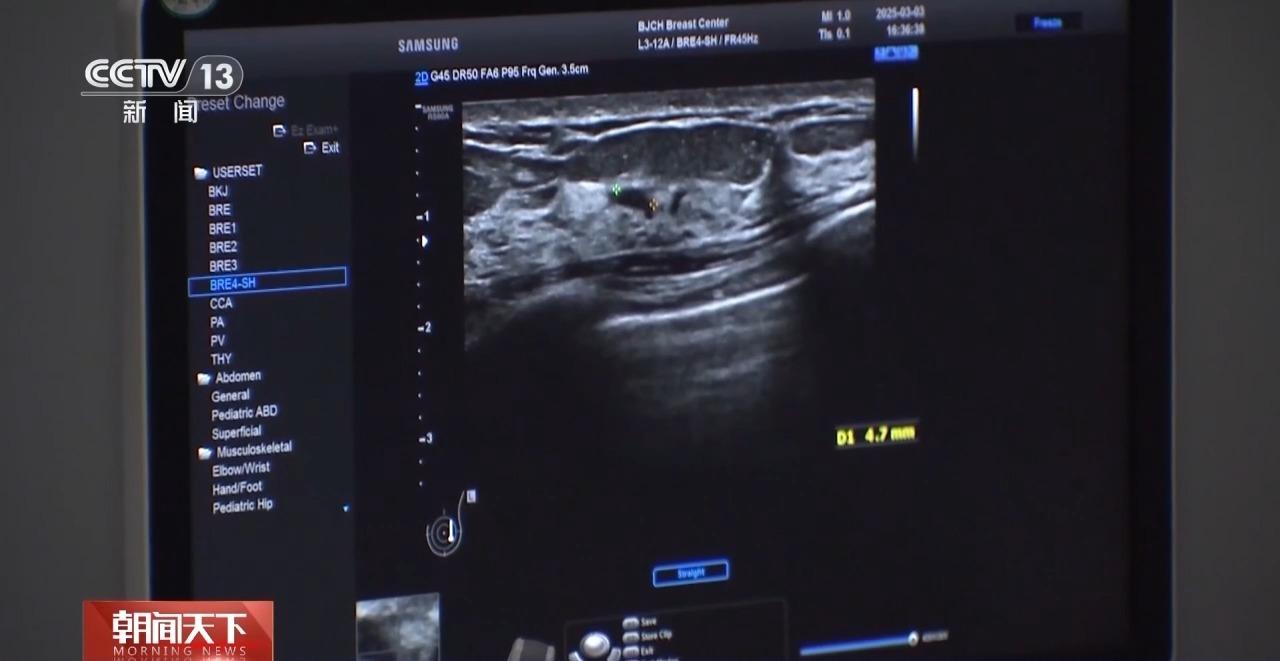

北京大学肿瘤医院乳腺癌预防治疗中心主任医师范照青一般来说我们推荐40岁以上的女性,1到2年做一次钼靶摄影,也推荐女性朋友每年至少做一次乳房的超声检查。钼靶检查有可能会发现极早期的乳腺癌,也就是说所谓的原位癌,它一般还没有发展成浸润癌的时候,是不会造成转移的,也就是说不直接威胁生命的阶段,我们把它发现及早处理掉。

钼靶和超声,是目前我国乳腺癌筛查的主要检查方法。两项检查,各有优劣,40岁以下的女性,一般来说,更适合做超声检查。

北京大学肿瘤医院乳腺癌预防治疗中心副主任医师霍苓(超声检查)首先是没有辐射,然后安全性好,所以不同年龄阶段的女性,年轻女性孕妇,还有需要频繁检查的女性都是可以经常做的。钼靶是一个X线检查,它是有辐射的,做的时候会把病人的乳房整个夹成一个片状,所以病人的耐受程度也会差一点。

虽然超声没有辐射,但对于微小钙化,钼靶检查的敏感性更高。

根据国际通行的BI-RADS分级标准,对结节予以0至6级分类。专家表示,3级以上的结节,女性需要重视,按时复查或尽快就诊。

北京大学肿瘤医院乳腺癌预防治疗中心副主任医师霍苓3级,一般半年要进行重复的超声检查;4级相对来讲恶性风险跨度比较大,一般建议要穿刺活检;5级的话就是高度怀疑恶性,所以一定要穿刺明确诊断,进行后续的治疗;6级就是已经在其他地方穿刺确诊为乳腺癌的病灶。